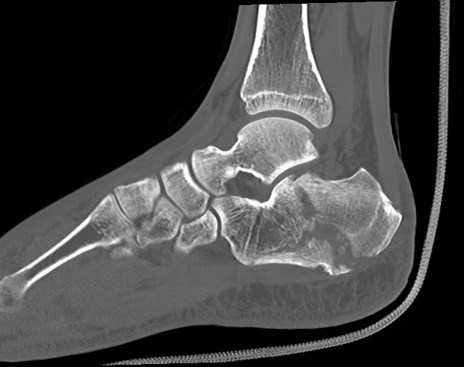

症例37 左足関節CT(矢状断像)

左足関節CT